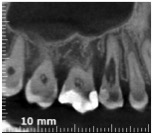

Quando nel 2013 mi è arrivato all’attenzione questo caso

Ho riconosciuto lo stesso fenomeno visto nella ragazza infestata da tessuti alieni di cui sopra e mi sono ricordato che all’università si era parlato di riassorbimenti esterni.

Allora ho studiato il fenomeno e ho saputo fare una diagnosi.

Si trattava di un riassorbimento esterno di classe IV.

Allora per capirci qualcosa in più ho fatto una cone beam.